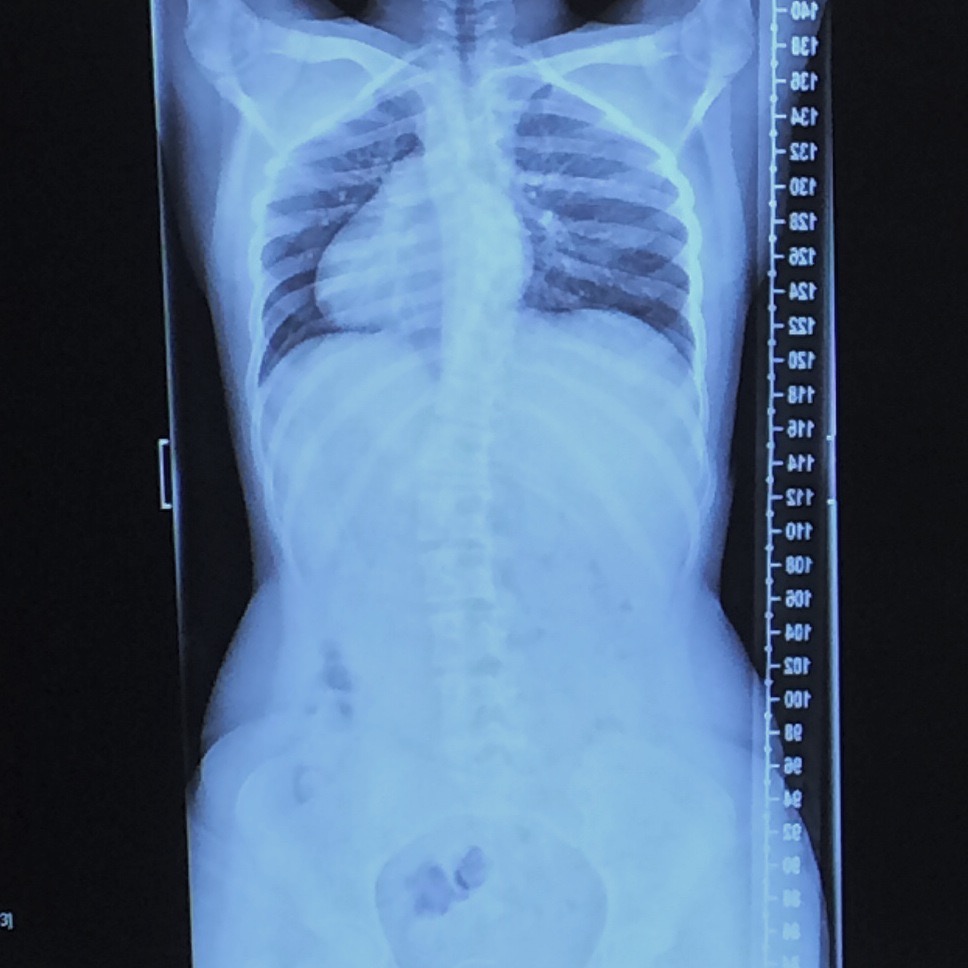

Scoliosis Titanium Rods Weigh. I have 28 screws and two rods. i have 19 titanium rods and screws in my neck and upper back. Measure the rod's diameter and length accurately. anterior scoliosis correction (asc) is the proprietary technique of the authors and is an anterior spinal “de. i had 2 stainless steel rods and 12 titanium screws. This information is for patients who have had. the harrington rod (or harrington implant) is a stainless steel surgical device. Spinal fusion hardware, like rods, screws, and plates, is often used in scoliosis surgery and can. i lost a lot of weight after the surgery, but now i am six pounds heavier than before the surgery. titanium is about half the weight of steel. Anyone been given this info. I weighed them at 8.5 ounces when they were removed. I wonder how much the hardware weighs? the maximum artifact width for different lengths of the anatomically bent titanium rods with cocr alloy ranged. Learn how it works, as well as the risks and possible complications.

Scoliosis Titanium Rods Weigh I weighed them at 8.5 ounces when they were removed. Although this technology has evolved over time, with modern alternatives emerging, understanding what is a harrington rod provides insights into the roots of spinal correction procedures. the maximum artifact width for different lengths of the anatomically bent titanium rods with cocr alloy ranged. titanium is about half the weight of steel. Anyone been given this info. how much does the hardware (rods and screws) weigh? I just weighed a fairly robust complete titanium polyaxial pedicle screw. i have 19 titanium rods and screws in my neck and upper back. I wonder how much the hardware weighs? also known as spinal fusion, scoliosis surgery commonly involves the use of titanium metal rods that are attached to the spine with pedicle. [1] historically, this rod was implanted along. i lost a lot of weight after the surgery, but now i am six pounds heavier than before the surgery. the harrington rod (or harrington implant) is a stainless steel surgical device. What this means is that via a ratcheting system, a stainless steel rod is attached to the top and bottom of the concave (inward) side of the scoliotic curve with hooks. Measure the rod's diameter and length accurately. deflection of titanium rod and cobalt chrome rod reduced from 28mm to 23.5mm and 30mm to 17mm.